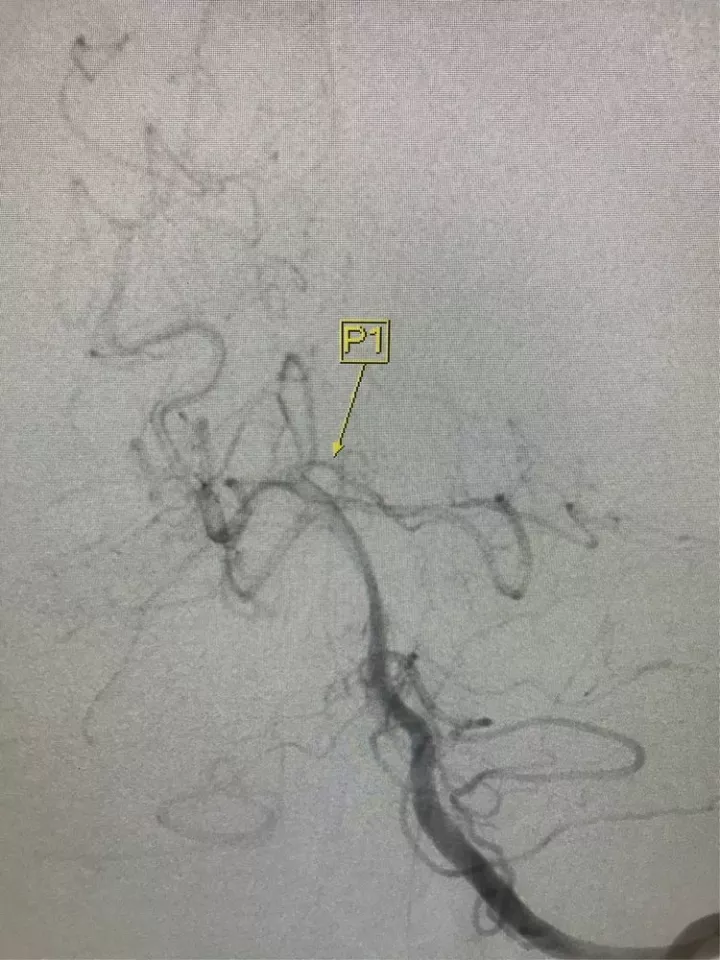

Enterprise4.5×22支架半释放,支架尾端的有效段能恰好覆盖全瘤颈

支架有效段完全释放,这个时候开始将支架导管往前顶,让导管头端尽量越过瘤颈远端

支架完全释放

释放后的造影。突入颈内动脉和后交通动脉内的弹簧圈被压入瘤体内

继续填塞,后面就简单了。最后的结果,一共用了四枚弹簧圈,栓塞致密,瘤体及破口都不显影了